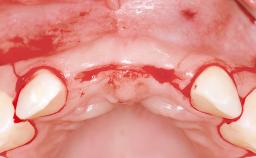

Replacement of Four Incisors with a Fixed Partial Denture on Two Narrow-Neck Implants after Implant Failure

| Jaw | Maxilla |

| Area | Anterior |

| # of Teeth | 4 |

| # of Implants | 2 |